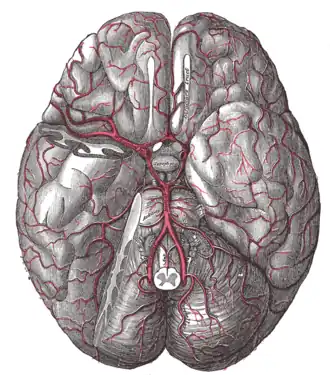

-

The arteries of the base of the brain.

The arteries of the base of the brain. -

Human brainstem blood supply